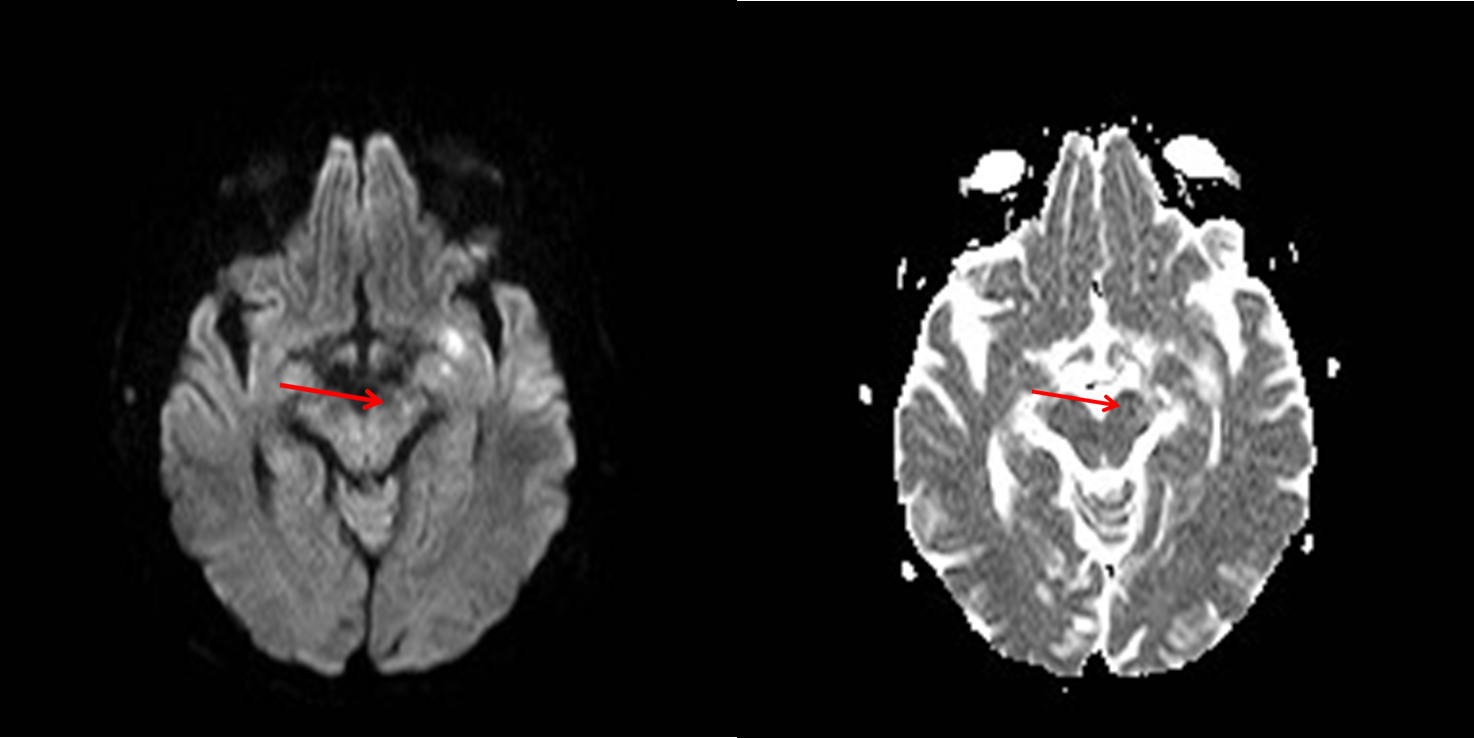

Se observa una lesión isquémica con una degeneración walleriana secundaria que también se observa en las secuencias de difusión y en el mapa ADC:

De una forma sencilla, la evolución de las alteraciones en la señal de la resonancia cerebral a lo largo del tracto de sustancia blanca refleja los cambios bioquímicos que ocurren durante la DW. Las alteraciones en la difusión que se muestra hiperintenso y la hipointensidad de señal en el mapa ADC sí que se han descrito en la fase aguda en la primera semana distal a una lesión por encima y son indicativas de degeneración walleriana. Serían los cambios más precoces detectables. Las alteraciones de la DW de las secuencias T2 suelen aparecer en la 3-4 semana aunque hay casos muy precoces que aparecen en las 2ª semana. Este caso es particular por el hecho que aparece precozmente.

Es importante revisar las imágenes y detectar los cambios precoces en las secuencias de difusión y mapa ADC distal a una lesión isquémica por las implicación pronóstica de las mismas.